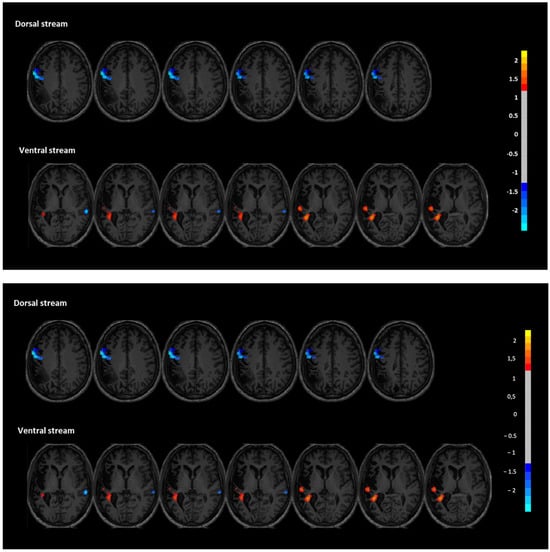

3.2. Resting-State fMRI Results

Functional connectivity (FC) analyses revealed distinct post-intervention changes in both the dorsal and ventral language streams, supporting a reorganization of language-related networks. In the dorsal stream, FC was significantly decreased in the left inferior frontal and precentral regions (peak coordinates: X = −60; Y = 0; and Z = 33), with a cluster size of 139 voxels and a z-score of −0.894. Note the following: These Z-scores represent voxel-wise differences between timepoints and may be lower than the initial ±2.5 threshold applied to the independent components, as explained in the Methods. This reduction may reflect a normalization or rebalancing of hyperconnectivity in perilesional motor-speech regions often observed in chronic aphasia. No significant increases were found in the dorsal regions of the right hemisphere. In contrast, the ventral stream showed signs of enhanced engagement. Specifically, two clusters within the left superior temporal gyrus demonstrated increased FC (X = −33; Y = −42; and Z = 12 and X = −54; Y = −24; and Z = 6), with cluster sizes of 109 and 12 voxels, and z-scores of 1.223 and 0.934, respectively. These changes suggest a strengthened role of left temporal areas, which are critical for auditory comprehension and phonological decoding. Additionally, decreased FC was observed in the right superior temporal region (X = −42; Y = 15; Z = −12), with a cluster size of 12 and a z-score of −0.806. This finding is consistent with the hypothesis that reducing maladaptive right-hemisphere overactivation may facilitate improved language function through interhemispheric rebalancing. Together, these findings suggest that the intervention facilitated plastic changes that increased connectivity of the left-hemispheric language network while downregulating compensatory activity in the right hemisphere, particularly in the ventral stream (Figure 4).

Figure 4. Functional connectivity changes in dorsal (top) and ventral (bottom) language streams after the intervention. Z-score maps show increased connectivity in left temporal areas (red) and decreased connectivity in right-hemispheric regions (blue). Color bar indicates voxel-wise Z-score differences between post- and pre-intervention resting-state fMRI.